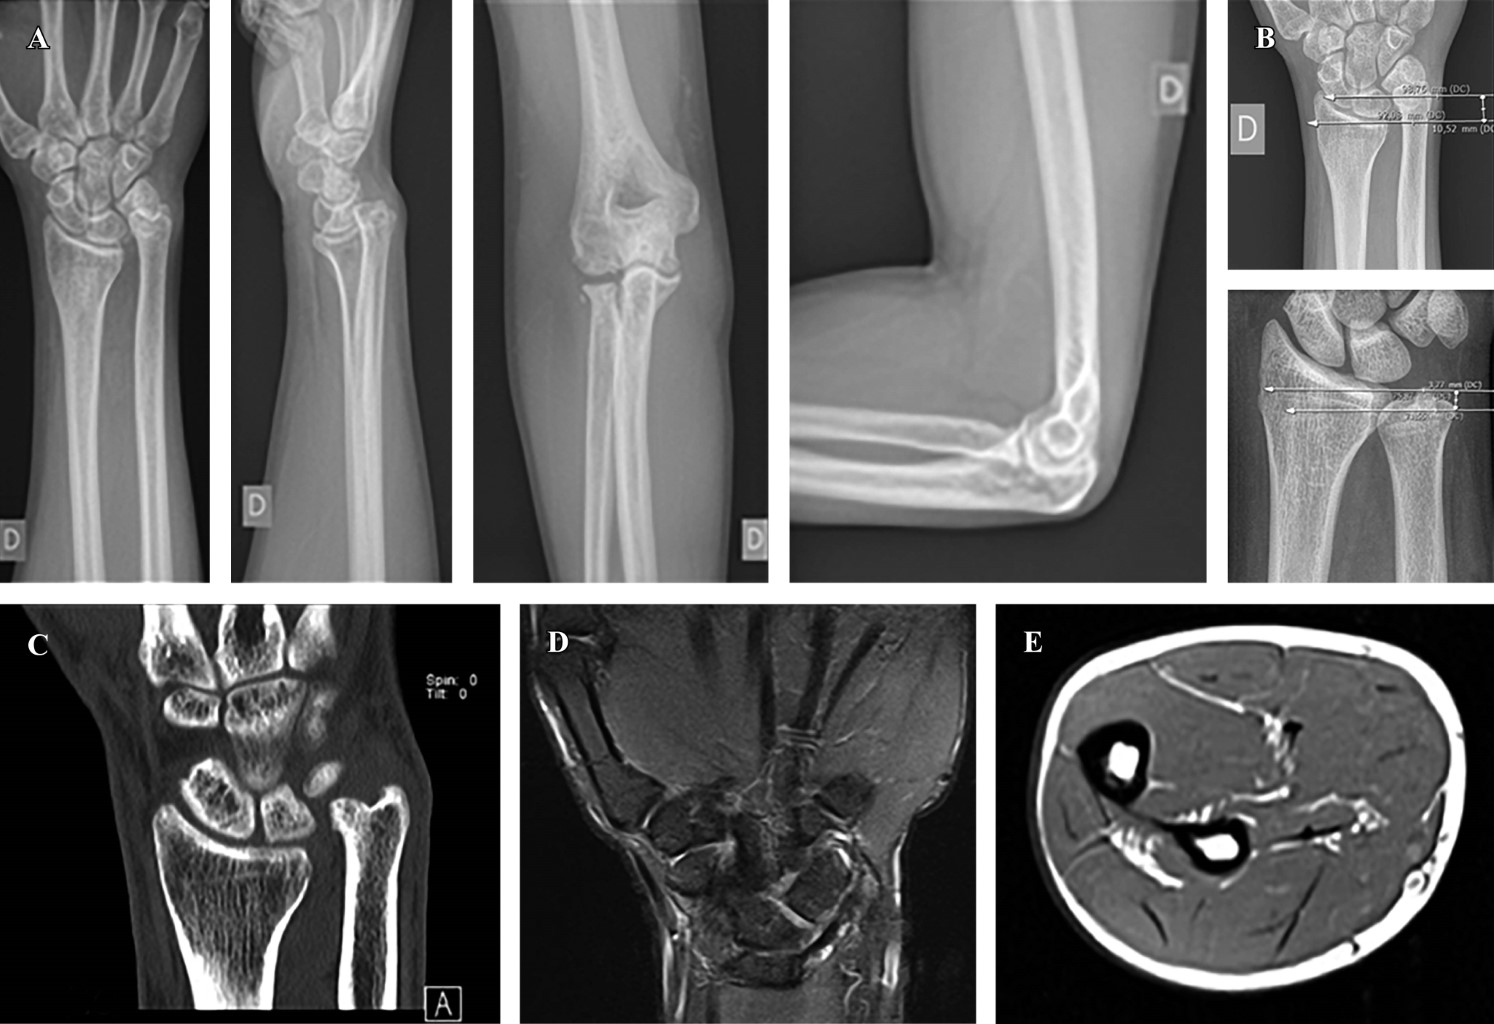

Introducción: el antebrazo puede considerarse como una articulación en sí misma donde interactúan el cúbito y el radio. Está constituida por la articulación radiocubital proximal (ARCP), la membrana interósea (MIO) con la banda medial como componente principal, y la articulación radiocubital distal (ARCD), que incluye el complejo fibrocartílago triangular (CFCT). La lesión de Essex-Lopresti (LEL) es una lesión compleja causada por una carga axial del antebrazo, que conlleva la disociación radiocubital longitudinal y la pérdida de estabilidad debido a la rotura de la MIO, la lesión de la ARCP con la cabeza del radio y lesión de la ARCD por afectación del CFCT. El diagnóstico precoz es crucial ya que el tratamiento de las lesiones crónicas plantea un importante desafío. Objetivo: describir la LEL crónica, revisar la literatura y compartir la experiencia de su tratamiento. Caso clínico: se describe el caso de un varón de 30 años que sufrió un accidente de moto en 2019. Diagnosticado inicialmente de fractura conminuta de cabeza radial derecha, fue tratado inicialmente mediante resección de la misma. El paciente visitó nuestro centro en 2023, la exploración clínica mostró dolor en muñeca y una protrusión dorsal de cúbito reductible pero inestable, sin dolor ni limitación de movimiento en el codo y antebrazo. Las pruebas complementarias, radiología simple y RMN, mostraron una varianza cubital positiva, una subluxación dorsal del cúbito a nivel de la muñeca y una lesión del CFCT, sin evidencia de ruptura aguda de la MIO. Se llevó a cabo un examen bajo anestesia y una evaluación fluoroscópica para examinar la estabilidad y el rango de movimiento del codo y la ARCD, así como la estabilidad longitudinal del antebrazo mediante tracción. Al no observarse inestabilidad longitudinal, se realizó una osteotomía de acortamiento del cúbito de 10 mm y se fijó con una placa y tornillos. De forma artroscópica, se observó la desinserción del CFCT y se reinsertó mediante una modificación de la técnica de Mantovani. Se inmovilizó con una férula de Münster. A los seis meses de seguimiento, tiene un EVA de 0 en codo y muñeca, y una flexión dorso/volar de 80º/80º, y un déficit de supinación/pronación de 10o/10o. Conclusiones: la LEL es una patología infrecuente pero desafiante para el cirujano. Las opciones terapéuticas incluyen diversas intervenciones quirúrgicas, siendo el acortamiento del cúbito con reparación del CFCT una opción viable en casos crónicos sin inestabilidad longitudinal.

Figura 3